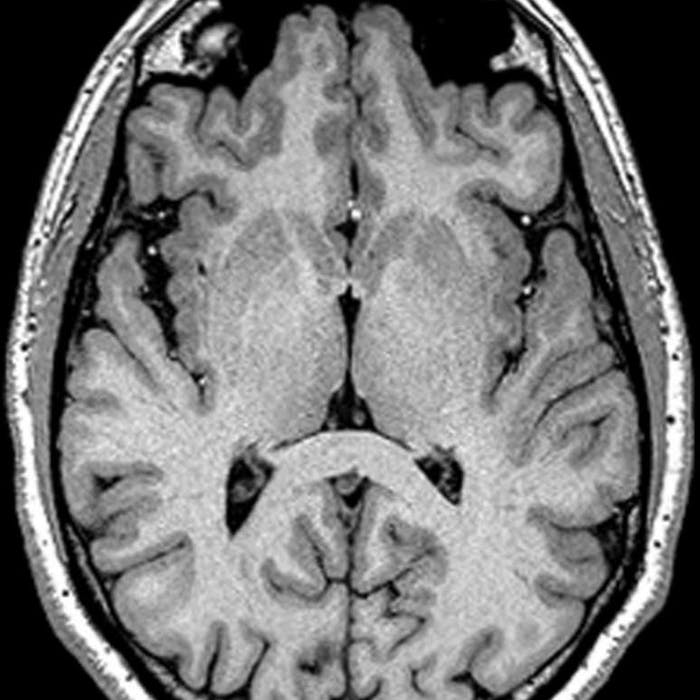

Heschl’s gyrus also called transverse temporal gyrus, is considered as a part of the temporal lobe and consists of Brodmann area 41 and 42 generally named as the primary auditory cortex. It is located adjacent to the other cortex named planum temporale (entirely responsible for the language formation) and superior temporal gyrus. It is entirely invaded and hidden within the Sylvian fissure of the human brain.

Anatomically, the transverse temporal gyri are discretely different from other temporal lobe gyri as they run from front to the backside in the brain but it runs toward the center of the brain (mediolaterally).